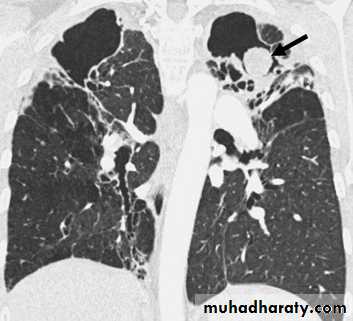

•Nodular (coin) lesion in the left upper lung with irregular edge (most probably cancinoma

•Differential diagnosis of multiple spherical lesions:

1 - Metastasis.2-Hydatid cyst.

3- Sarcoidosis.

4- Rheumatoid nodules.

5 – pneumoconiosis

6- Histoplasmosis

Chest X-ray shows radio-opaque (white) nodular lesion in the right mid-lung field.

Dx:x chicken pox , Histoplasmosis (calcified granuloma).CAVITARY LESIONS